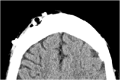

Complications related to Ventriculoperitoneal shunt placement are common, and multiple. Among them blockage and infection. We report a case of 44 years old man admitted to our hospital after an obstruction of his ventriculo-peritoneal shunt by an air bubble that caused behavioral problems and confusion. The patient was operated twice, the last time the puncture point had to be changed. The follow up was marked by a clear clinical improvement. Shunt malfunction continues to be a common neurosurgical problem in patients with shunted hydrocephalus, often leading to frequent and sometimes lengthy hospital stays. This case illustrates the management of this rare situation causing air bubble shunt obstruction.